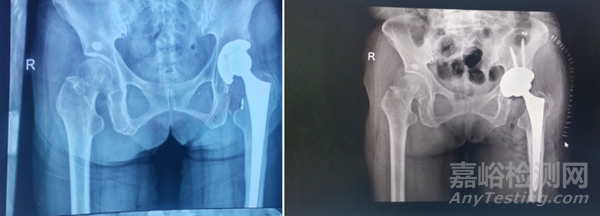

左圖:術(shù)前髖臼內(nèi)襯磨損 右圖:髖關(guān)節(jié)翻修術(shù)

這里特別說一下髖關(guān)節(jié)表面置換術(shù),它使用金屬假體置換股骨頭,其中金屬髖臼組件的作用就是建立一個金屬與金屬的承載面,承載面的反應(yīng)與質(zhì)量會限制它的應(yīng)用,例如會出現(xiàn)假體磨損、感染、松動等情況。

根據(jù)澳大利亞相關(guān)數(shù)據(jù)表明,表面置換術(shù)后的5年累積翻修率顯著上升,如何提高材料的抗疲勞度呢?